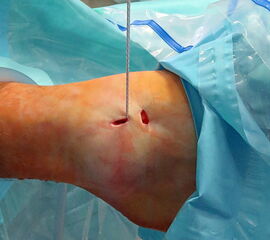

Nachfolgend wird die OP-Technik an einem rechten Sprunggelenk unter Verwendung von PEEK-Ankern veranschaulicht.

-

Abbildung 4 -

Abbildung 5 -

Abbildung 6 -

Abbildung 7a -

Abbildung 7b -

Abbildung 8a -

Abbildung 8b -

Abbildung 9a -

Abbildung 9b -

Abbildung 10 -

Abbildung 11 -

Abbildung 12 -

Abbildung 13 -

Abbildung 14 -

Abbildung 15 -

Abbildung 16 -

Abbildung 17 -

Abbildung 18 -

Abbildung 19 -

Abbildung 20 -

Abbildung 21 -

Abbildung 22 -

Abbildung 23 -

Abbildung 24 -

Abbildung 25a -

Abbildung 25b